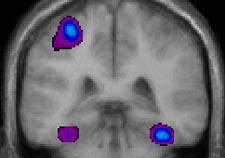

Coupe coronale en

TEP durant la tâche d’imitation avec la main droite : l’activité

principale a lieu dans le cortex moteur de l’hémisphère gauche

et l’activité secondaire dans les deux cortex visuels ventraux.